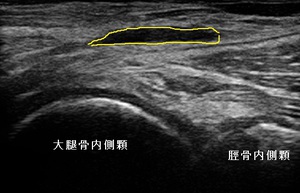

左ひざ裏内側 超音波長軸像 同部 穿針排液18日後

超音波観察を行ったところ、膝窩内側にベーカー嚢腫が認められました。(左上画像の黄色の囲み)

女性の嚢腫は、かなり大きくなっていましたので、依頼先クリニックで穿針排液してもらうことにしました。約20mlが

吸引されたと報告を頂きました。右上画像は排液18日後ですが、嚢腫が縮小している様子が確認できました。